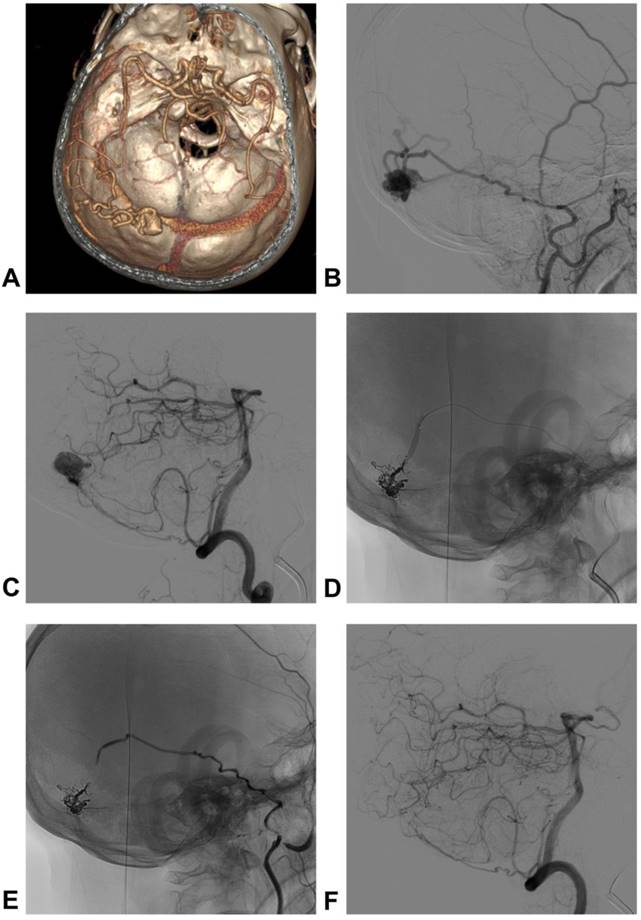

A 48-year-old man who presented with subarachnoid hemorrhage was admitted to our hospital. The DSA showed a TSS DAVF, and the feeding arteries included the petrous branch of the MMA and PMA. The venous drainage presented with cortical venous reflux. The TSS DAVF was embolized by PD of the MMA via a double-lumen balloon, which is known as the pressure cooker technique. After TAE, the TSS DAVF was cured. The typical case is shown in Figure 2.

Figure 2

Images of a typical case. A: CTA shows the dilated veins on the left TS, suggestive of DAVF; B: DSA of the left ECA shows the TS DAVF; PD of the MMA was the main feeding artery, and cortical venous reflux was observed; C: DSA of the vertebral artery showed that the PMA was also a feeding artery; D: the TS DAVF was embolized by PD of the MMA via a double-lumen balloon, which is known as the pressure cooker technique; E-F: DSA of ECA and vertebral artery show that the TS DAVF was cured. Abbreviations CTA: computed tomographic angiography; TS: transverse sinus; DAVF: dural arteriovenous fistula; DSA: digital subtraction angiography; ECA: external carotid artery; PD of the MMA: posterior division of middle meningeal artery; PMA: posterior meningeal artery.